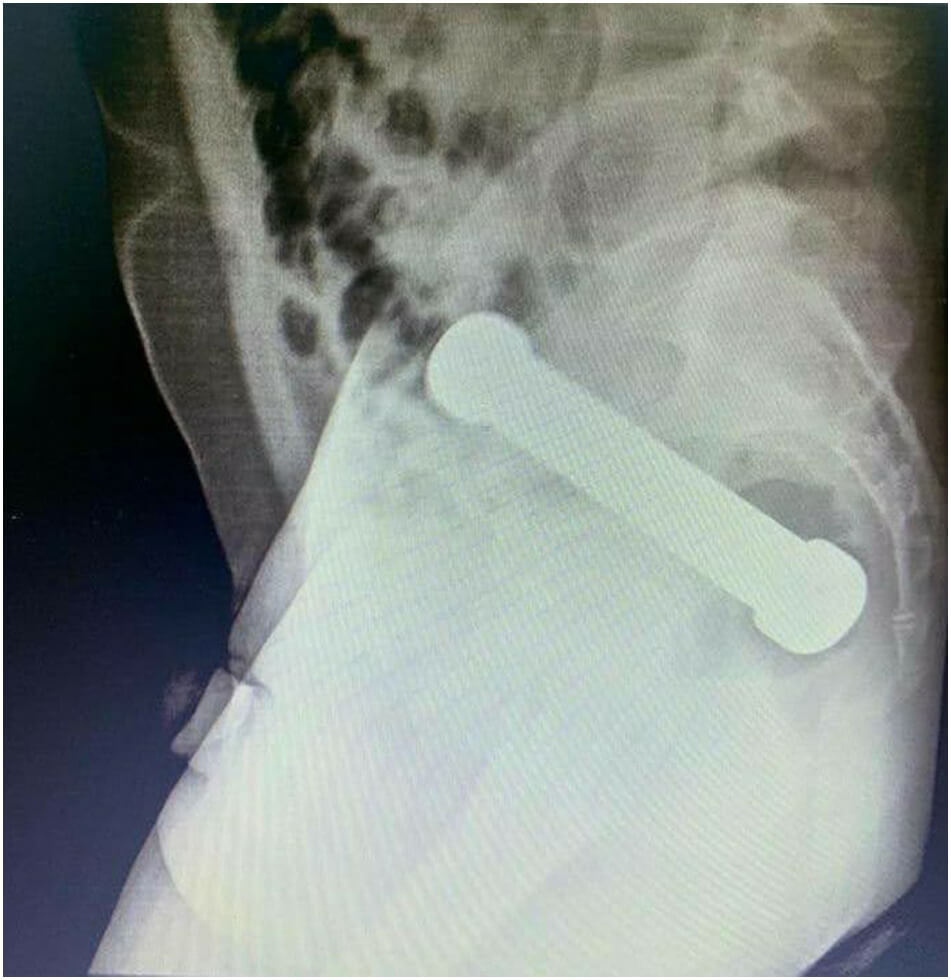

Göğüs ve karın radyografisinde, pnömoperitonyum yokluğu, inen, enine ve çıkan kolon anslarında hafif distansiyon ve rektosigmoid geçişte yaklaşık bir yerde egzersiz dambıl şeklinde yabancı bir cismin varlığının kanıtı

Bahse konu operasyona ilişkin ilgili makalede yer verilen görseller şu şekildeydi: